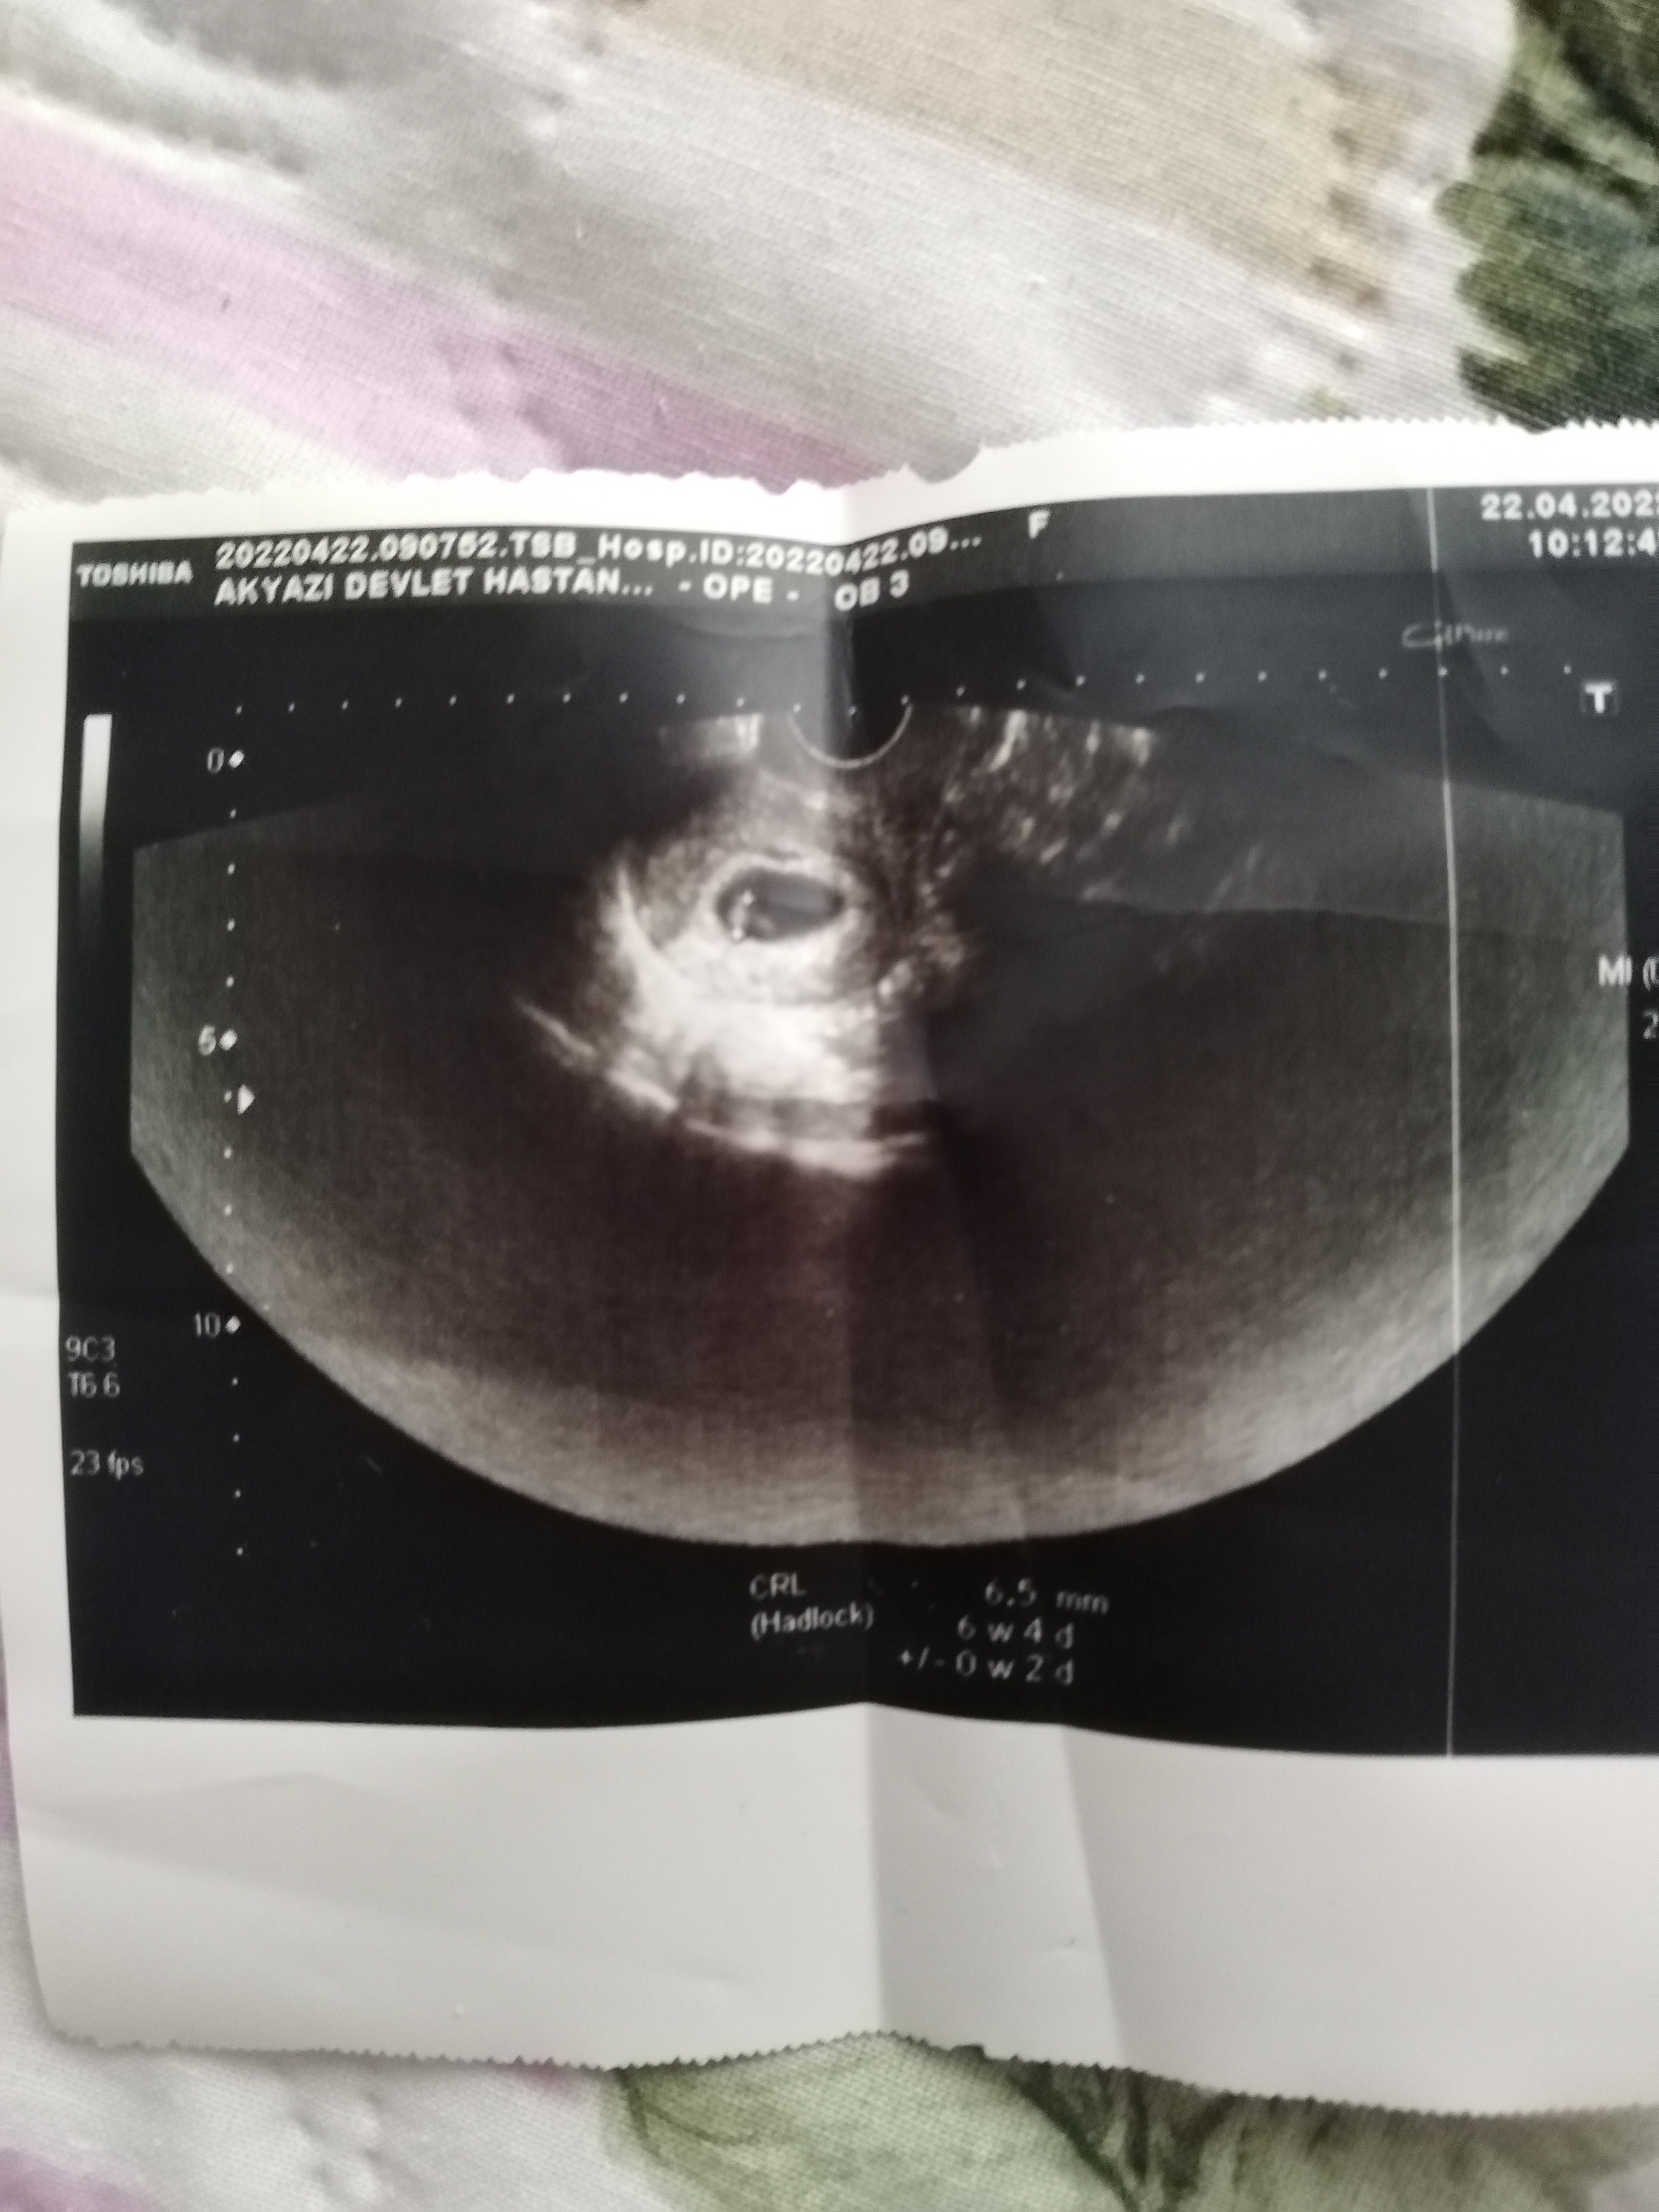

Canım bunlar Altan gözüktü sadece baş popo mesafesj var crl diye 6+4 pko olduğu için geç döllenme daha gitmedm doktora kalp atisii icin 7+7 yiz bugün

En alttaki ultrasonda ki kağıtta 0 w2 biseyler yazıyor o nedemk cnm 4+6ykende 1w 0di o gram mi oluyor

Gittim cnm 6+4 haftalık ta doktor bana bebeği gösterdi kesede aşırı gazım şişkinlik göğüs ağrısı vardı ama kalp atışlarını duyamadm işte ufak dedi